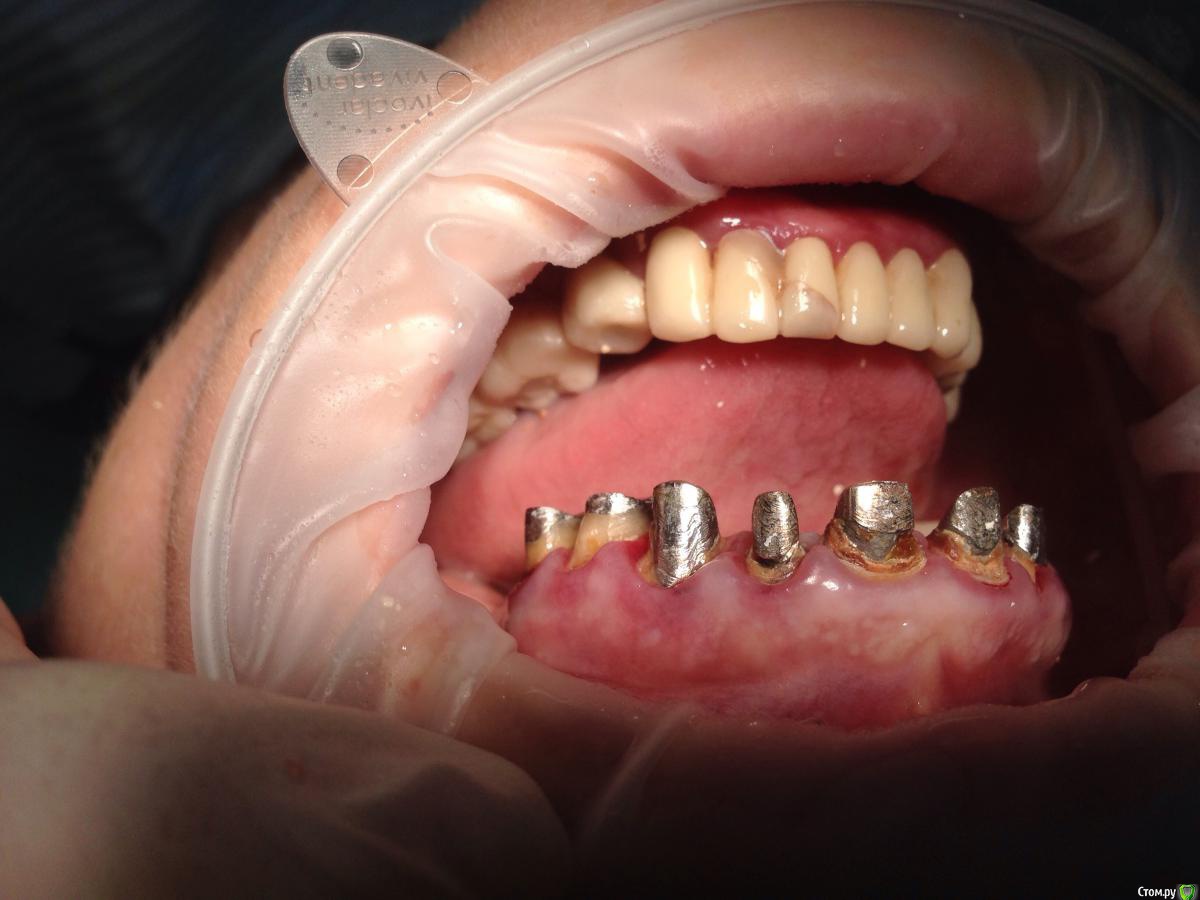

Bratok Опубликовано 17 июля, 2016 Поделиться Опубликовано 17 июля, 2016 Коллеги, всем привет! Вот такая пациентка в клинике был доктор у нас с 20 летним стажем, она уехала сейчас и не работает. Протезировала пациентку.. Были изготовлены временные коронки.. Судя по всему страдал герметизм и под ними все печально.. Десне и феррулу хана...Чтобы Вы тут посоветовали? Планировалось к нее мк... Сделать в 3 сегмента 3-3 и остальные блоком. Какой прогноз? Лет 5? Извиняюсь за качество rg.. Ссылка на комментарий

AndyAndy Опубликовано 17 июля, 2016 Поделиться Опубликовано 17 июля, 2016 Привет! М-да, печаль беда.... Мы же с вами понимаем что все это надо извлекать, убирать кариес и смотреть на то что останется. Возможно хир удлинение коронковой части. Пациентка как настроена вообще? вы наверняка объяснили ей чем она рискует. Но все- таки стремно так все оставлять. Там герметизм нарушен и между вкладками и стенками канала, 100%. Ссылка на комментарий

Bratok Опубликовано 17 июля, 2016 Автор Поделиться Опубликовано 17 июля, 2016 там нарушено все, что могло быть нарушено Ссылка на комментарий

korotkevich Опубликовано 17 августа, 2019 Поделиться Опубликовано 17 августа, 2019 (изменено) Коллеги, всем привет! Вот такая пациентка в клинике был доктор у нас с 20 летним стажем, она уехала сейчас и не работает. Протезировала пациентку.. Были изготовлены временные коронки.. Судя по всему страдал герметизм и под ними все печально..Десне и феррулу хана...Чтобы Вы тут посоветовали?Планировалось к нее мк...Сделать в 3 сегмента 3-3 и остальные блоком. Какой прогноз? Лет 5?Извиняюсь за качество rg..В идеале доставать вкладки, убирать кариозные ткани, делать билдапы и затем либо хирургическое удлинение, либо вертипреп, либо и то, и другое; и металлокерамические коронки с гирляндой, таким образом сохраните максимально то, что есть Изменено 17 августа, 2019 пользователем korotkevich Ссылка на комментарий